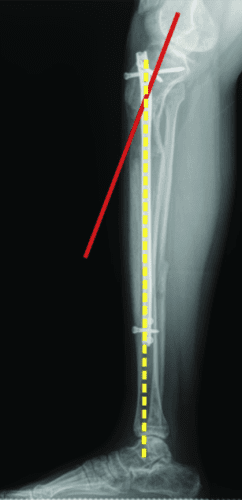

过早合并示意图1

图1:延长量细微差异

过早合并示意图2

图2:X光片确认诊断

轴向偏斜是胫骨中更常见的问题。胫骨往往会延长成外翻和外翘。为防止这种情况,钉子应插入正确的起点,该起点非常高,并且尽可能靠后,在胫骨的外侧,并在额平面的膝盖中心。如果指甲与截骨术上方的外侧皮层之间有空间,则应在该空间中插入阻挡螺钉。如果指甲与后皮层之间有空间,则在那里插入另一个阻挡螺钉。我设计了 STRYDE 钉子,通过提供第三个近端锁定螺钉(P2.2 只有两个)来抵抗轴向偏差。如果遵循所有这些预防措施,则不会随着延长而出现屈曲或外翻畸形。

敲击(外翻)鞠躬(内翻)

屈曲(procurvatum)

在外部机构胫骨身材延长并出现双侧并发症的患者。他发展了胫骨和 Abu/a 延迟结合,右侧是敲击 {外翻),左侧是弓形 {内翻),两侧是 f1exion {procurvatum}。我们在手术室使用临时外部斧头机对两侧进行了急性矫正,并放置了新的胫骨杆。我们在 Abu/a 延迟结合上放置了逆行杆。